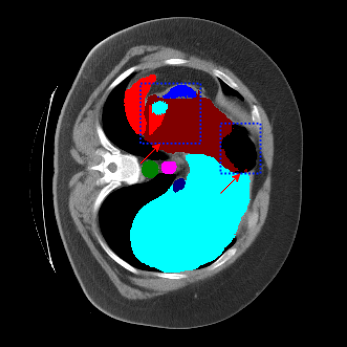

| Ground Truth | LoGoNet | DiNTS Search |

|---|---|---|

![]() |

We begin by qualitatively inspecting our model. Figure 3 compares the output of LoGoNet to the best performing baseline model in BTCV dataset, i.e., DiNTS Search (more qualitative comparisons can be found in appendix section 11). We see that our model particularly excels in segmenting organ boundaries. This can be attributed to our effective strategy for extracting local-range dependencies, which plays a crucial role in extracting details from input data. Our model’s adeptness in capturing long-range dependencies allows it to grasp contextual information that extends over significant distances within the data. Simultaneously, its proficiency in handling short-range dependencies ensures precision in capturing localized patterns.